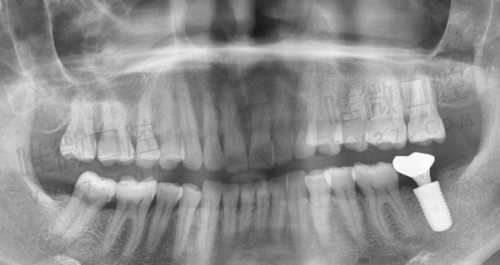

2026年在北京大学口腔医院种牙,价格主要看种植体品牌。

国产的莱顿种植牙4000元起,创英5500元起;韩国登腾5300元起;

欧美进口的就贵了,瑞士ITI 9020元起,德国费亚丹11200元起,瑞典诺贝尔11700元起。

半口种植12万起,全口种植21万起。

这里要提醒大家,价格还包含手术费,比如种一颗瑞士ITI,种植体1.2万+手术费5000元,总价1.7万左右。偷偷告诉你,如果预算有限,可以考虑国产种植体,现在技术也特别成熟了!